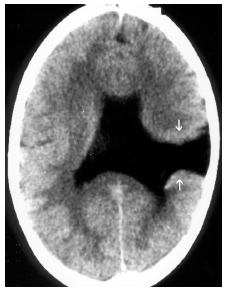

Diante desse quadro neurorradiológico e da imagem apresentada, qual é o diagnóstico?